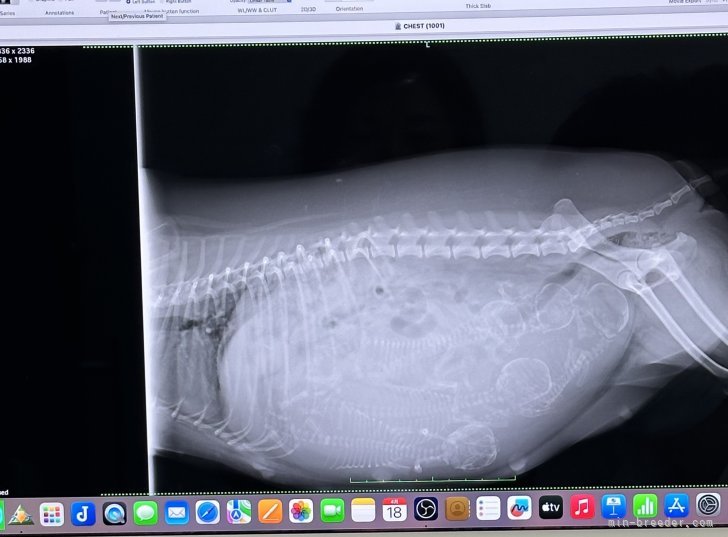

蓮華(ブラック)さんの妊娠1年ぶりにママになる、蓮華さん🤰✨ 今日は、レントゲンに行ってきた時のお写真です。 看...

もう、すぐそこ六花(ホワイト)の、お産が そこまできています。 もう、いつ生まれても大丈夫! レントゲ...

順調でしたブラウンお母さん お腹のベビーは、順調。 骨盤も問題なさそうです。 まぁ、いつも安産です...

無事に全頭(トイプードル)本日、レントゲンいってきました。 エコーのときと、頭数変わらず。 みんな、無事でした。 ありが...

最終確認(トイプードル)ホワイトお母さん 最終の、赤ちゃんの頭数確認に 行ってきました 初期の確認→4匹 最終確認→...

最終頭数(トイプードル)初めのエコーでは3匹! と言われていた ブラウンお母さんのメル。 最終エコーと、レントゲンを ...

小休憩?本日も、ポメラニアンベビー紹介 と 思いましたが。 シルバーお母さんの 出産がちかくなり、レン...